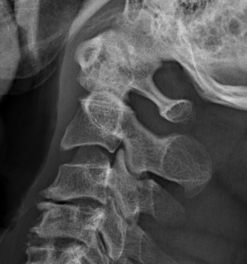

Xray

Atlanto-dens interval (ADI)

Space available for Cord (SAC) / posterior atlanto-dens interval (PADI)

1. AADI (anterior atlantodental interval) > 3 mm

2. Instabilty

A. Instability : > 3 mm difference in flexion / extension views

B. Severe instability: > 7 mm difference

Instability 3 mm

Severe instability